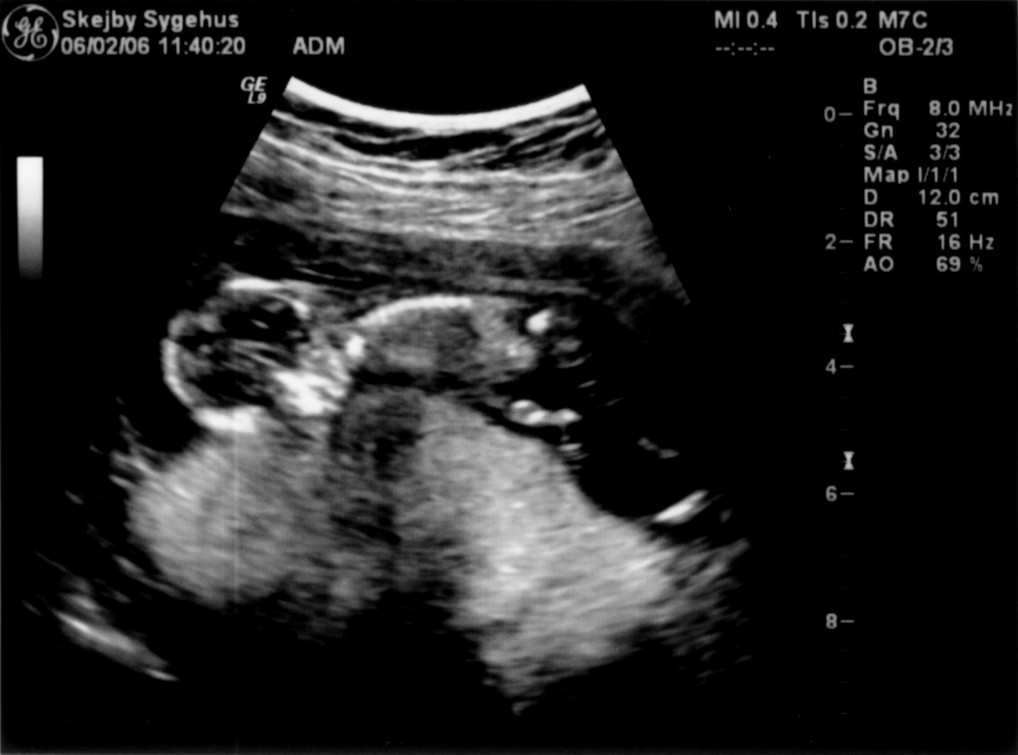

Ultralydsskanning den 6. februar 2006

Vi har i dag været på Skejby Sygehus og få foretaget en ultralydsskanning af baby. Der var kun én (pyh)! Baby blev målt og gennemset for eventuelle misdannelser. Der blev set efter at kraniet var begyndt at blive dannet og at der var to hjernehalvdele. Vi så to arme og to ben og der var fem fingre på den hånd vi så. Vi så også hjertet slå. Til sidst blev der blev målt bredden på nakkenfolden for at vurdere risikoen for mongolisme. Konklussionen var, at alt var som det skulle være. Du kan se de billeder vi fik fra skanningen herunder.